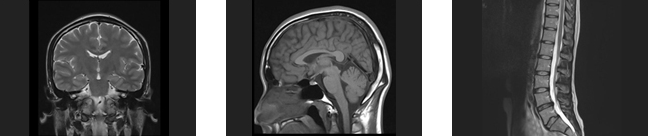

MRI検査

MRIとは、磁気共鳴断層画像診断装置(MagneticResonanceImaging)の略です。

X線検査やCT検査のようにX線を使わず、強力な磁石を埋め込んだトンネルの中に入り、電波を身体に当てることで体内の状態を断面像として撮影する事ができます。種々の撮像法の実用化により、コントラストのよい高精細な画像を比較的短時間に提供できるようになり、特に、脳・脊椎・四肢・骨盤腔(子宮、卵巣、前立腺)の病変に関しては、優れた検出能力を持っています。

早期アルツハイマー型認知症診断システム(VSRAD)

当院では、早期アルツハイマー型認知症診断システム(VSRAD)を用いた検査が可能です。

【VSRAD】とは、頭部MRI検査で撮影された画像を用いて、アルツハイマー型認知症に特徴的に見られる海馬傍回付近の萎縮の形態画像情報を解析して、診断の支援情報を提供するものです。現在当院が使用している最新のVSRAD advance 2では、アルツハイマー型認知症(AD)とレビー小体型認知症(DLB)の鑑別診断を支援する参考指標が追加されました。 通常の頭部MRI検査と同時に撮影ができ、約7~8分の追加ですみます。

※ この検査だけで認知症の診断が確定するわけではありません。診察や他の検査結果との総合的な判断により診断されます。少しでも物忘れの心配がある方は神経内科医師にご相談下さい。